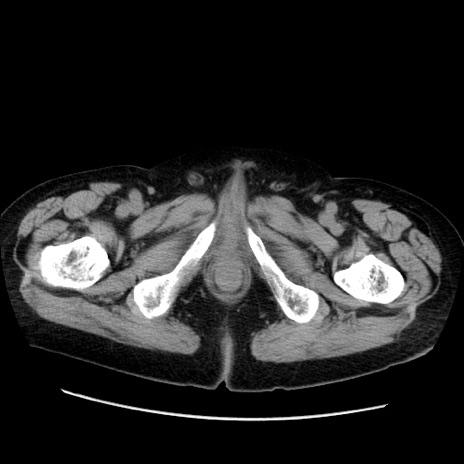

冠状断像